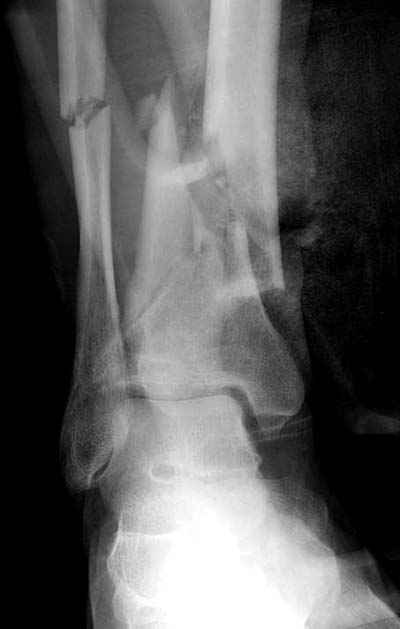

На представленных рентгенограммах укорочения по длинне, т.е. смещеия в таранно-тибиальном суставе - нет. Истинная картина появится поле устрнения смещения по длинне большеберцовой кости.В любом случае нужно предполагать 3-ий вариант.

Все более банально - разрыв межкостной мембраны выден на исходном снимке - внимательней рассмотрите расстояние между берцовыми костями выше и ниже места перелома большеберцовой кости - Вам станет это понятно и без МРТ. А интраоперационно на малоберцовой кости пришлось сопоставлять не дистальный отломок к проксимальному, как это обычно приходится делать при переломе лодыжки, а наоборот - проксимальный отломок к дистальному. т.к. проксимальный отломок малоберцовой кости нестабильной из-за разрыва межкостной мембраны.

Представляю рентгенограмму перелома обеих костей голени, где определяется разрыв дистального межберцового синдесмоза.

Механизм травмы - подвернул ногу. На боковом снимке видно, что латеральная лодыжка поломана на уровне голеностопного сустава. Во время травмы, кроме воздействия крутящего момента на кости голени, происходило еще и стремительное движение тела больного вниз вместе с проксимальным отломком малоберцовой кости (сила земного притяжения), вследствие чего разрывается межкостная мембрана, передняя межберцовая связка (lig.tibiofibulare anterius), рудиментарная поперечная связка. На боковом снимке конец проксимального отломка ( в данном случае место прикрепления передней межберцовой связки) находится на уровне середины таранной кости. Соответсвенно, последняя разорвана. Смещение отломков костей голени по длине - около 2 см.

Соответственно, из составляющих ДМС осталась целой

лишь задняя межберцовая связка. Хирургу, который будет оперировать пациента, рекомендовано наложить шов передней межберцовой связки, и ввести позиционный винт выше ДМС.